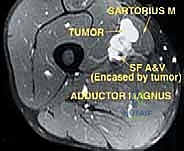

* Angiography: Performed to assess the tumor's vascularity, detect any "tumor blush" (indicating high-grade malignancy), identify feeding vessels, and most critically, determine if the femoral artery is merely displaced or directly invaded by the tumor.

FIG 2 • B. Angiogram of the same lesion showing tumor blush from the late arterial phase.